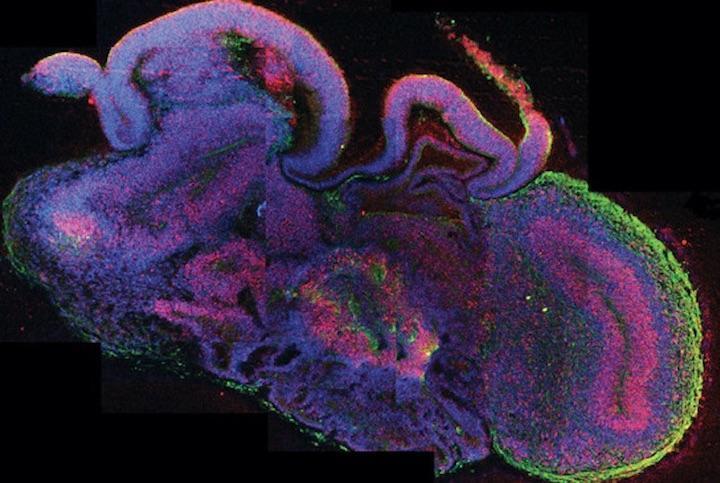

Технология использования стволовых клеток для создания небольших трехмерных моделей органов человека достигла больших успехов за последнее десятилетие или около того. В частности, создание искусственных мозговых органоидов размером с фасоль, сделанных из человеческих плюрипотентных стволовых клеток, является одной из самых горячих областей современной нейронауки.

Исследовательская работа, опубликованная в 2017 году исследовательской группой Гарвардского университета в США , показала, что «церебральные органоиды развивают различные ткани, такие как нейроны коры головного мозга и клетки сетчатки», а в апреле 2018 года Институт Soak Когда исследовательская группа пересадила человеческий мозг органоидов в мозг мыши были обнаружены функциональные синаптические связи.